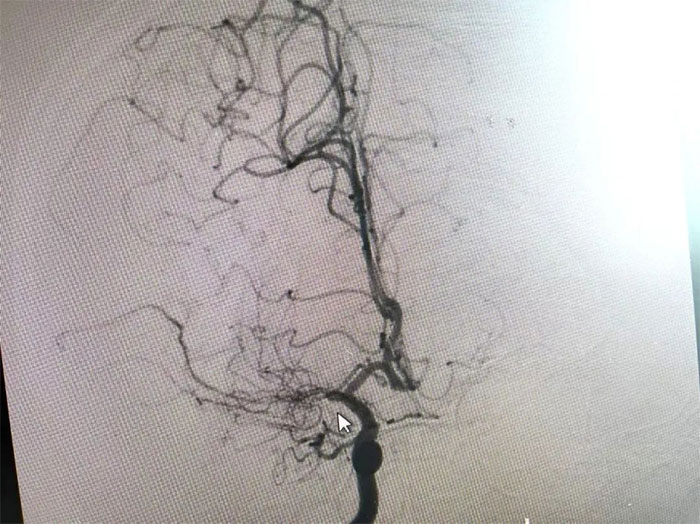

在與患者及家屬充分溝通后,李振并主任為周先生展開了DSA(數(shù)字減影血管造影)檢查。

在檢查中發(fā)現(xiàn),周先生右側(cè)大腦中動脈M1段閉塞,可見煙霧狀異常血管網(wǎng)生成;左側(cè)大腦中動脈M1段重度狹窄(約70%)。符合煙霧病的典型影像學(xué)特征。

▲ 檢查發(fā)現(xiàn)煙霧狀異常血管網(wǎng)

煙霧病又名Moyamoya病,腦底異常血管網(wǎng),是一組以Willis環(huán)雙側(cè)主要分支血管(頸內(nèi)動脈虹吸段及大腦前、中動脈,有時也包括大腦后動脈)起始部慢性進行性狹窄或閉塞,繼發(fā)出現(xiàn)側(cè)支異常的小血管網(wǎng)為特點的腦血管病。因腦血管造影時,呈現(xiàn)許多密集成堆的小血管影,似吸煙時吐出的煙霧而得名。